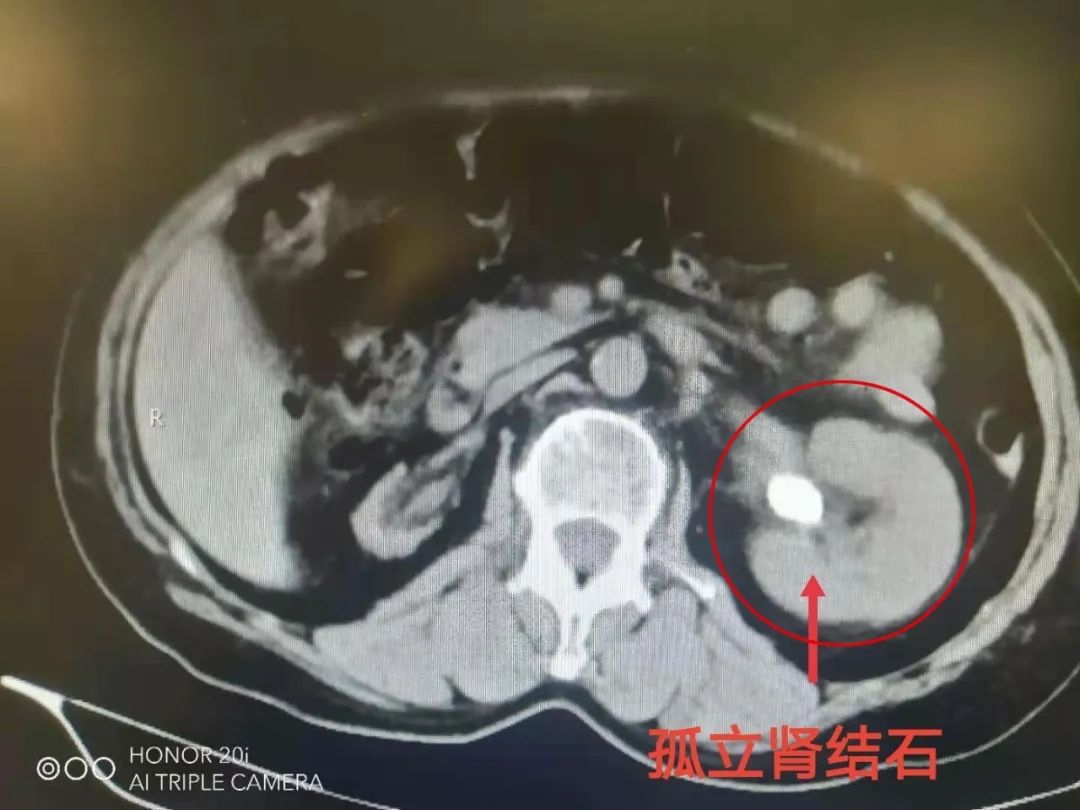

术前拍片,最大结石接近3cm吕夷松博士团队给黄阿姨进行了细致检查,并会诊讨论,诊断为左肾功能性孤立肾、左肾多发结石,结石较大,最大接近3cm。

术后片子显示,结石已取净经过缜密地手术规划,充分的术前沟通。

手术非常顺利,时间仅1小时,术中无出血,术中及术后经X线检查显示左肾结石完全取净。